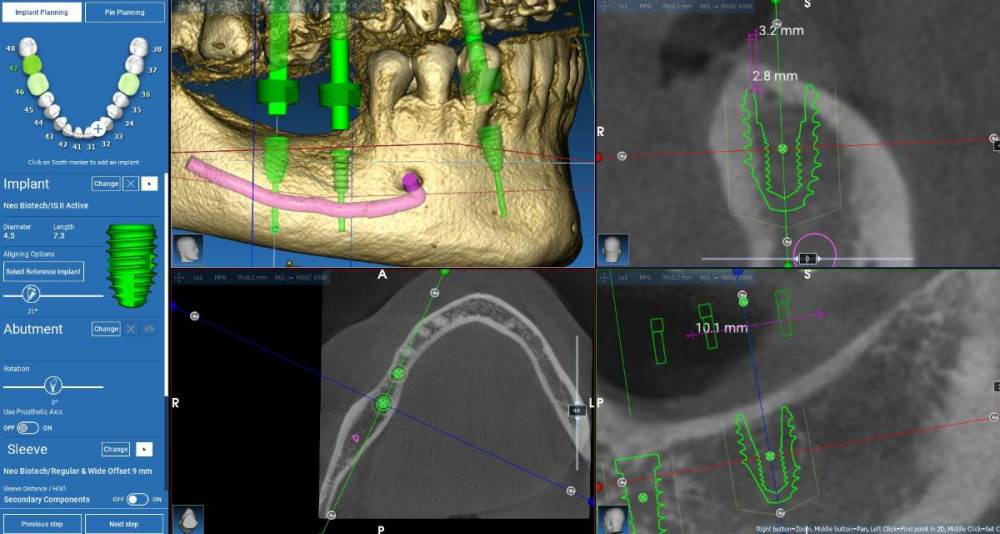

Fin Опубликовано 1 ноября, 2021 Поделиться Опубликовано 1 ноября, 2021 Здравствуйте коллеги. Очень нужно Ваше мнение. Что бы Вы сделали в четвертом сегменте? 1. Анкилос 3.5 х 6.6 в обл. 4.6 и необиотек 4,5(мб 5) на 7.3(0,5). 2. НКР (по ширине) Блоком или титановой сеткой в об 4.6 и после необиотек 4.5 на 7.3( полир шейка пол мм). В области 4.6 тоже что и в первом случае. 3. НКР при помощи спейсера на импланте в области 4.6 (импл 4 на 7,3). В области 4.6 тоже что и в первом случае. 4. Необиотек 4 на 7,3+сст на шейку импл. В области 4.6 тоже что и в первом случае. 5. Ваша вариант. Естественно работа с десной для создания кератинизированной слизистой в всех случаях. Протезирование скорее всего с уровня МЮ. Ссылка на комментарий

Fin Опубликовано 2 ноября, 2021 Автор Поделиться Опубликовано 2 ноября, 2021 4 часа назад, kamranchick сказал: под коллагенновую мембранку, ауто со сверла, в области шейки импланта ауто, далее ксено, дистальный импл еще заглубить можно Вы бы поставили 4х7.3. на 4.6 и небольшую сосиску? Дистальнй да,+- 0,5 мм глубить, думал мб взять 5х7,3 с полир шейкой в 1,3. Пугает, что коротышки получаются. Ссылка на комментарий